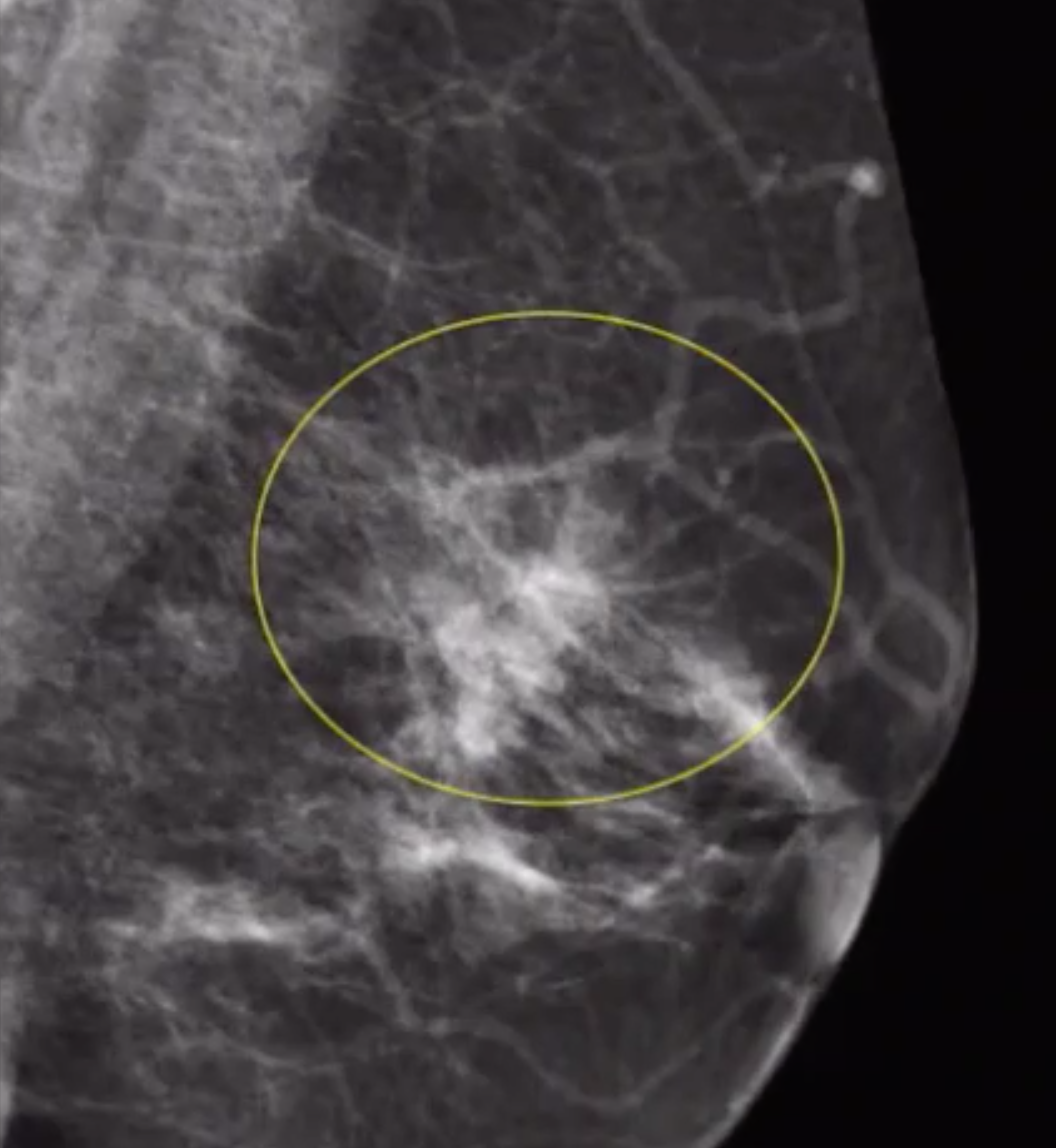

Architetcural Distrotion

• DDx

• Malignancy - IDC-NOS, ILC

• Radial Scar

• Post-surgical scar

Architectural Distortion